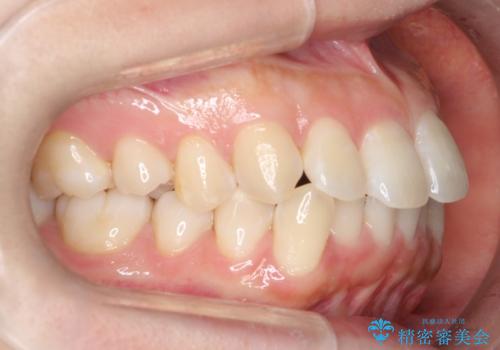

- 前歯のがたつきを主訴に来院されました。初診時、右上2番の口蓋側転位と右下7番の舌側傾斜が認められました。

インビザラインにてIPRと歯列弓拡大を行い、ゴム掛けで噛み合わせを改善する治療計画を立てました。

マウスピースの使用時間が短いため、シュミレーション通り進むか不安でしたが

治療期間1年で、主訴である前歯のがたつきを改善出来、

奥歯の噛み合わせも良くなりました。